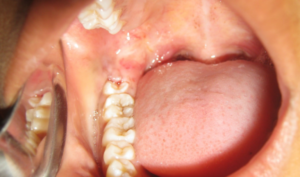

Ощущение болезненности при начавшемся росте зуба возникает в каждом втором случае, и ее основной причиной является травматизация располагающихся над зубной коронкой мягких тканей десны и их воспаление. Воспалительным изменениям предшествует механическое повреждение, неудовлетворительная гигиена полости рта и большое скопление налета, пищевых и микробных частиц под десневым капюшоном.

Воспаление десневого капюшона над зубом мудрости

Десна становится отечной и болезненной, а при присоединении бактериальной микрофлоры появляется гнойное отделяемое, ухудшается общее самочувствие.

При тяжелом течении перикоронарита поднимается температура тела, могут возникать нарушения проглатывания пищи из-за отечности смежных структур, наблюдается припухлость щеки на стороне патологии, увеличение околоушных и подчелюстных лимфатических узлов.